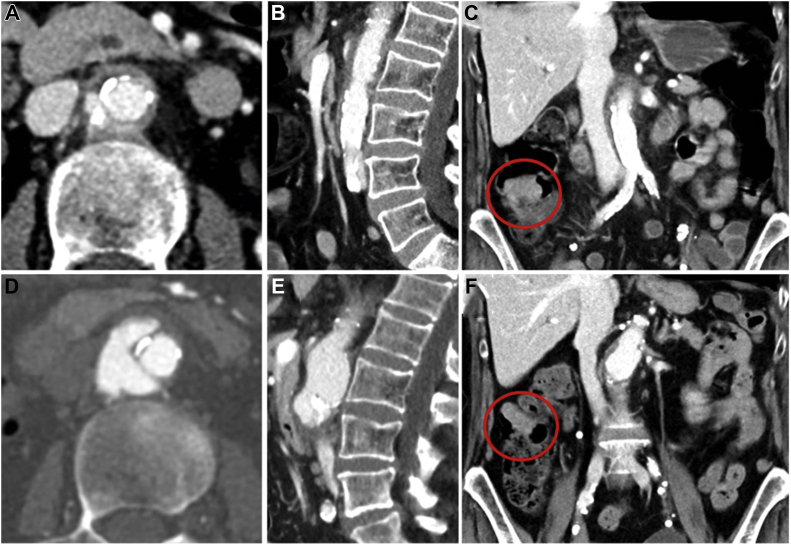

Fig 2.

Computed tomography (CT) scans at diagnosis (A-C) and at 3 months of follow-up (D-F). After 3 months of antibiotic treatment, progressive aneurysmatic growth (+12 mm) of the juxtarenal aorta was found with a wide penetrating ulcer and dissection of the outermost vessel layers at a craniocaudal expansion of 5 cm. The tumorous structure in the right colon is highlighted with red circles(C and F).

The inflammatory parameters were within the normal range, and the patient had not had any symptoms at 3 months of follow-up. The interdisciplinary and ethical board evaluation rejected an attempt of aortic repair at this stage and agreed to further antibiotic treatment in consensus with the patient and her close family, aware of the imminently fatal end due to rupture. Thus, no further diagnostic or interventional treatment was administered because such treatment was rejected by the patient. The patient did not undergo curative intended colorectal surgery, and the colonic mass was left untouched. However, the patient was in satisfactory condition at the 6-month follow-up and, ultimately, died of rupture after 8.9 months (266 days).